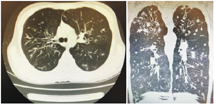

移植前1年患儿活动后胸闷、气促,需吸氧治疗,超声心动图提示三尖瓣反流、肺动脉压轻度增高,胸部CT(图1)示双肺支气管弥漫性扩张、管壁增厚,尤以上肺为著。移植前肺功能:FEV1 39.2%,用力肺活量(FVC)79.9%,呼气峰流速(PEF)59.1%。经评估,患儿反复出现呼吸道感染,FEV1<40%预测值,日间静息状态需氧疗,肺动脉压增高,符合肺移植手术适应证,无禁忌证,于2019年10月(17岁1个月)行双肺移植,术后病理示肺组织内广泛急慢性炎症细胞浸润,多发脓肿灶形成,炎症以支气管周显著,部分支气管腔内脓栓形成。肺组织局部纤维化明显。移植后9个月胸部CT示气管支气管通畅,右肺中叶少许炎性病灶,胸膜未见明显增厚(图2)。术后1年复查肺功能:FEV1 80%,最大肺活量(maximum vital capacity,VCMAX)86.6%,PEF 86.9%,一口气呼吸法肺一氧化碳弥散量(carbon monoxide diffusing capacity single breath method,DLCOSB)81.3%;术后1年9个月肺功能:FEV1 79%,VCMAX 88.4%,PEF 81.6%,DLCOSB 86.4%。至2022年3月,术后2年余,患儿身高166 cm,体重45 kg,无咳嗽、咳痰,活动正常,可爬海拔500余米的山,监测血氧饱和度正常,复查超声心动图正常,移植术后胸部CT示气管支气管通畅,右肺中叶少许炎症病灶,胸膜未见明显增厚。